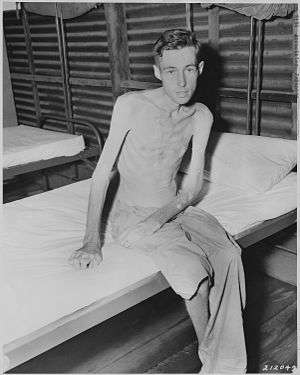

| Prisoner of war exhibiting muscle loss as a result of malnutrition | |